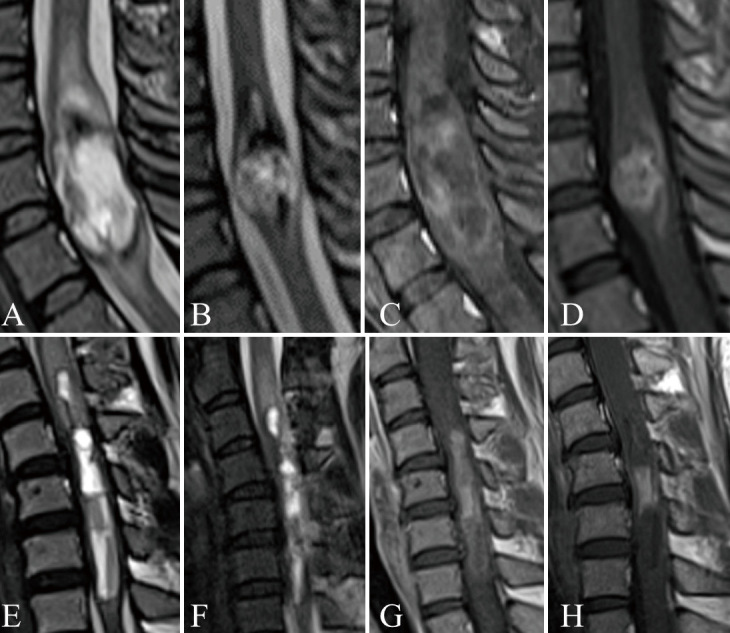

Spinal ependymomas are common intramedullary tumors that can show dynamic changes in magnetic resonance imaging findings over time. This study aimed to analyze these imaging changes and their implications for perioperative management. The retrospective study included patients diagnosed with World Health Organization grade 2 spinal ependymoma who underwent surgical resection and had at least 2 preoperative magnetic resonance imaging scans. Patients were divided into 2 groups based on the presence or absence of radiographic changes on magnetic resonance imaging. Magnetic resonance imaging analyses included non-contrast T1- and T2-weighted images, as well as gadolinium-enhanced T1-weighted images when available. Key features evaluated included intraparenchymal edema, hemosiderin deposition, syringomyelia, and cyst components. Changes in tumor size and contrast enhancement patterns were documented. Radiographic changes were identified in 4 out of 15 cases (26.7%). All cases with imaging changes exhibited hemosiderin deposition or hemorrhage, significantly higher than in cases without changes (100% vs. 18.2%, p < 0.05). No significant differences were observed in the presence of cystic components, syringomyelia, or edema between the groups. In the group with radiographic changes, the timeframe for these changes in the images ranged from 3 days to several years. Spinal ependymomas can demonstrate dynamic magnetic resonance imaging changes during the preoperative period, including both growth and reduction in tumor size. The presence of hemosiderin deposition or hemorrhage might be associated with these imaging changes. Proper timing of magnetic resonance imaging is crucial for informing surgical planning and optimizing treatment strategies for patients with spinal ependymomas.

Abstract Image